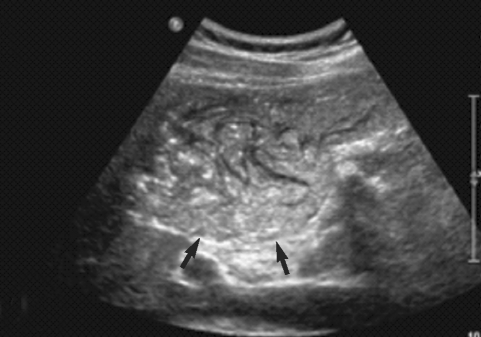

An Imported Case of Echinococcosis of the Liver in a Korean Who Traveled to Western and Central Europe

The Korean Journal of Parasitology 2010;48(2):161-165.